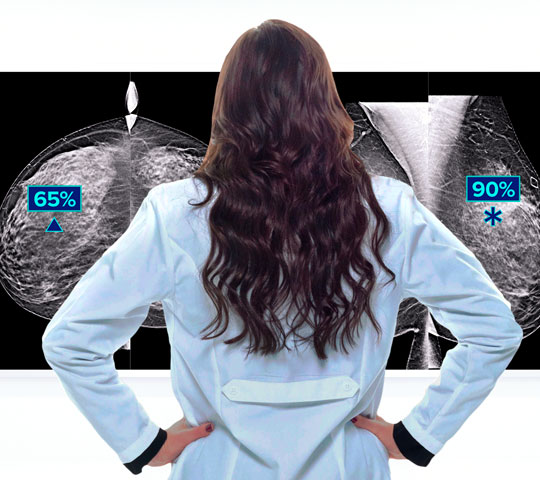

Elevates Mammography AI Technology

SecurView 12.0 workstations integrate the latest imaging technologies from Hologic such as 3DQuorum® imaging technology, Hologic Clarity HD® high-resolution imaging technology, and Genius AI® Detection 2.0 software.

Optimized Genius® AI Detection 2.0 software synergy

SecurView 12.0 software introduces intelligent new functionality with Genius™ AI Detection automated lesion correlation markings between CC and MLO views.